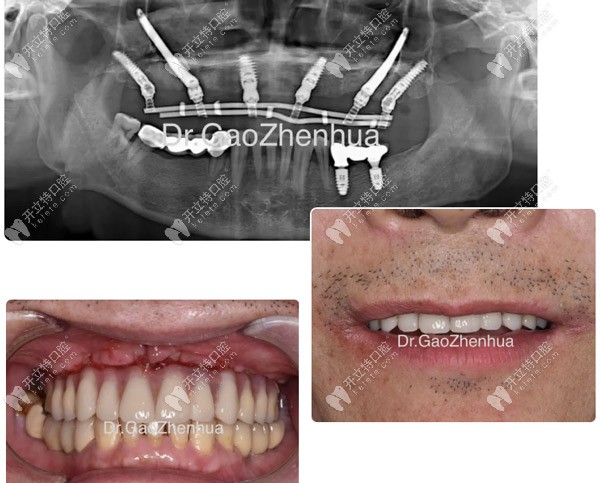

顴種植位點不得已還是放在貫通位點,竇底適當植骨,前牙區(qū)靠鼻底硬骨板雙皮質(zhì)固位獲得穩(wěn)定性,經(jīng)過2個小時的手術(shù),實現(xiàn)了即刻負重的預(yù)期!

當天做完VIIV穿顴穿翼手術(shù)

當天做完VIIV穿顴穿翼手術(shù)▲

鼎植口腔的VIIV穿顴穿翼是一項針對口腔缺骨顧客實現(xiàn)即刻種植、即刻完成固定牙修復(fù)的技術(shù)。

即便是重度牙槽骨萎縮、骨質(zhì)疏松、糖尿病及高齡人群也可以通過穿顴穿翼技術(shù)實現(xiàn)即刻種植的效果。